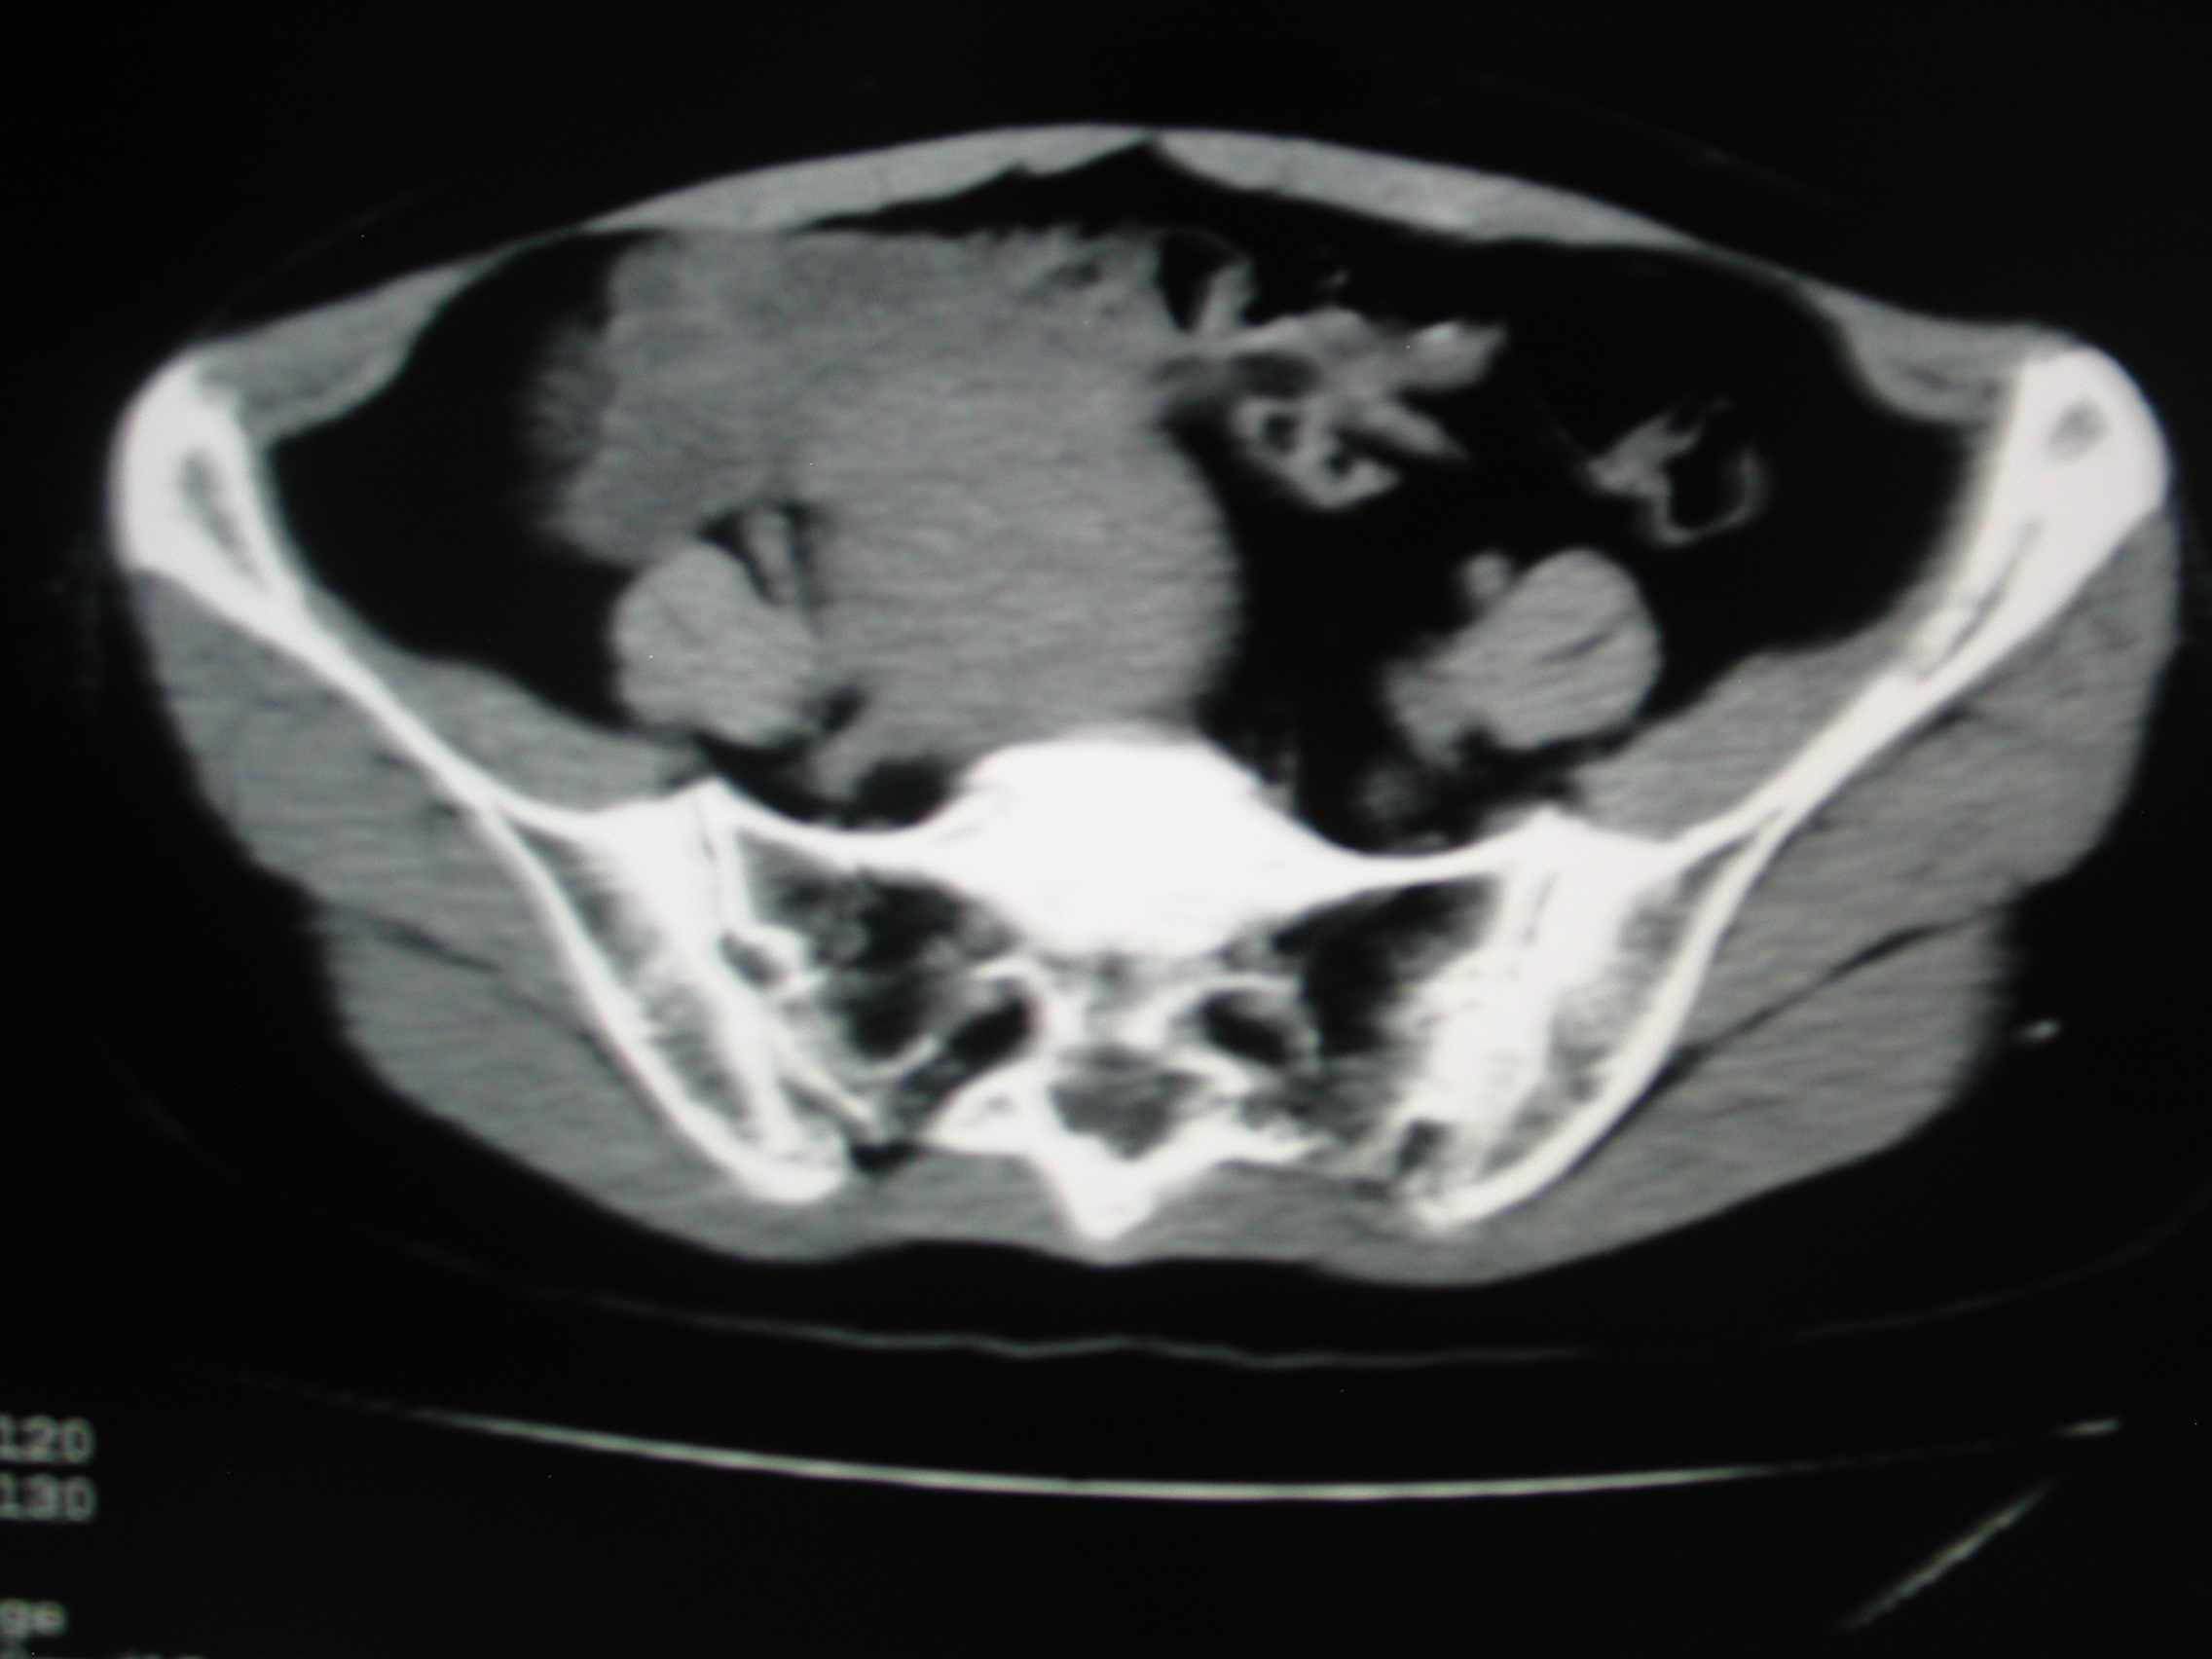

CT50860:女.46岁;超声子宫肌瘤。

本帖最后由 cefcmj 于 2015-7-18 17:16 编辑 瘤体外的一圈低密度是什么?

手术 子宫肌瘤 右侧附件区未见异常。 ( 瘤体外周线圈样低密度为其对子宫肌的压迫形成。或为瘤体外周一层疏松组织.假包膜。)

子宫及周围可见巨大软组织密度包绕,右侧附件区见低密度影,考虑巨大子宫肌瘤,右侧卵巢囊肿可能。

巨大子宫肌瘤,右侧附件区低密度影,考虑聚集的肠管。

盆腔巨大肿块,密度不均匀,与子宫相连,支持巨大子宫肌瘤;右侧附件区囊性病变,考虑卵巢来源囊肿可能性大。